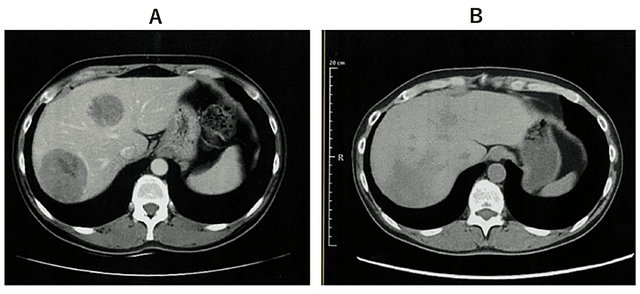

宫颈癌:联合治疗方案实现肝转移灶清零

2024年3月28日,医学期刊《Cureus》报道了一例晚期宫颈癌患者通过WT1-DC疫苗+纳武利尤单抗等联合疗法成功实现肿瘤完全消退的突破性病例。

患者为50多岁女性,既往接受了手术、放化疗,但很快便出现淋巴结转移(右锁骨上窝、气管旁)及肝转移。更改方案1个月后肝转移灶仍旧快速进展。

由于肝脏60%体积已被两个巨大转移灶占据,接受全肝放疗后,转移灶显著缩小。随后,医生尝试创新性免疫联合疗法:肾母细胞瘤 1 脉冲树突状细胞疫苗疗法(WT1-DC)+纳武利尤单抗。幸运的是,第5次WT1-DC注射后,CT显示肝转移灶完全消失。治疗期间出现高热(≥39°C),但可自行缓解。